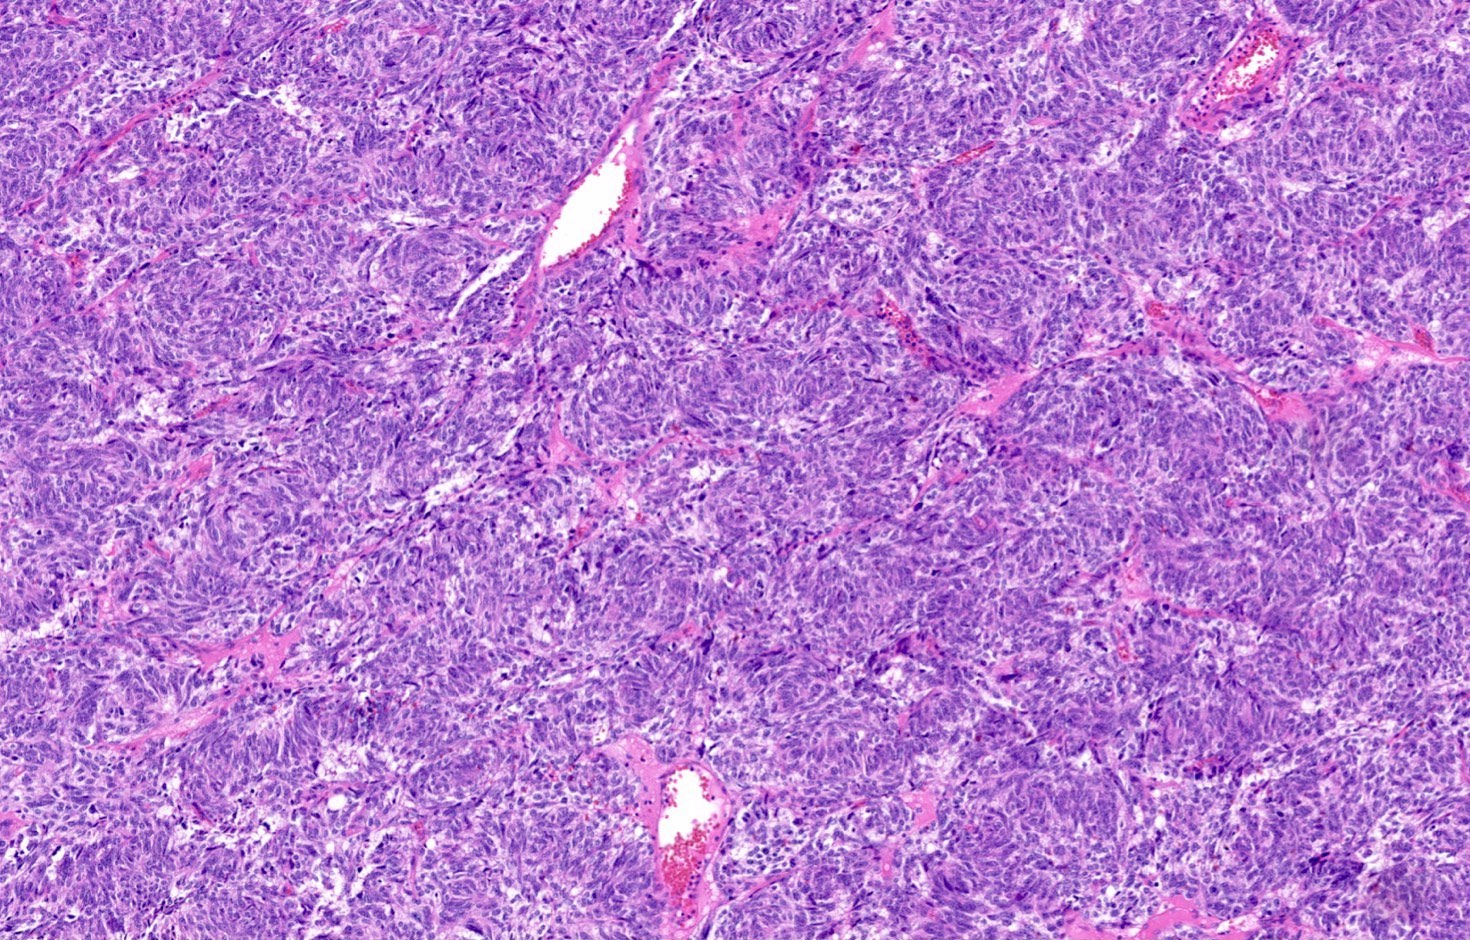

Microscopic (histologic) description

- Diagnostic criteria

- Neuroendocrine tumor with size ≥ 5 mm with < 2 mitoses/2 mm2 and absence of necrosis

- Neuroendocrine growth pattern (organoid, trabecular, rosette formation, nested) or pseudoglandular, follicular and papillary growth

- Tumor cells are uniform with a polygonal shape, round to oval nuclei with salt and pepper chromatin as well as inconspicuous nucleoli and moderate to abundant eosinophilic cytoplasm

- Spindle cells and clear cell features can be seen

- Stroma is fine and highly vascularized; hyalinization, cartilage or bone formation are possible

- Reference: Curr Oncol 2018;25:S86

Microscopic (histologic) images

Contributed by Philippe Joubert, M.D., Ph.D., Jijgee Munkhdelger, M.D., Ph.D. and Andrey Bychkov, M.D., Ph.D.